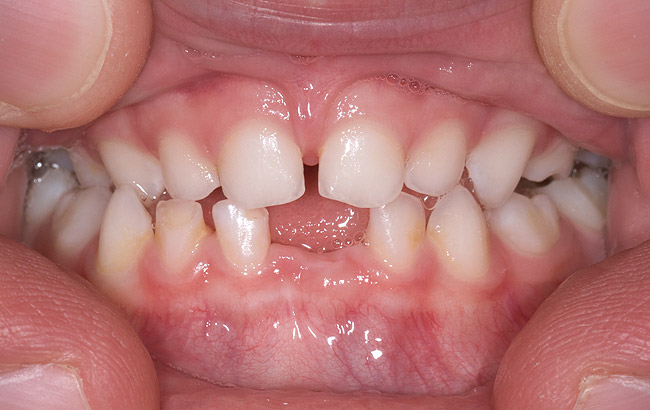

(14.) Angle Class III occlusion with constricted maxilla.

Figure 14

(15.) Cephalometric evaluation demonstrates significant tonsillar blockage of the airway and bimaxillary retursion.

Figure 15